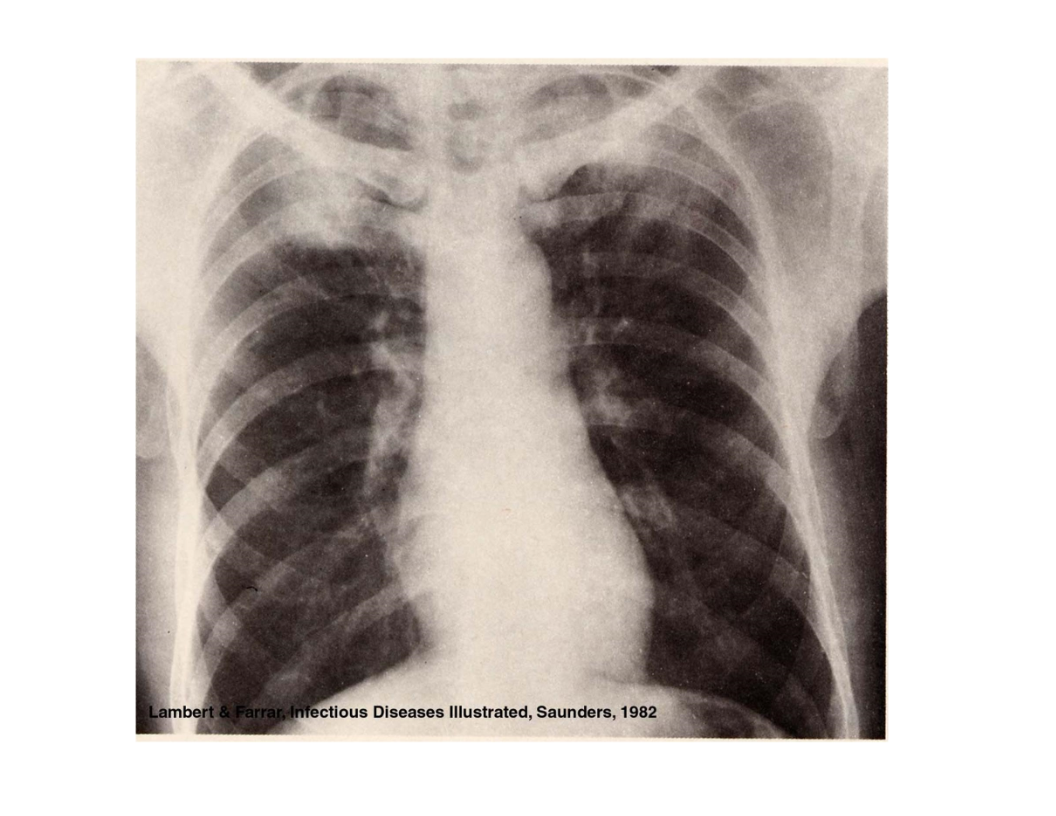

pulmonary TB:

chronic productive cough with blood0tinged sputum

cavities or infiltrates are often seen in the apex of the lung

upper lobe pulmonary lesions if reactivation is in the lungs